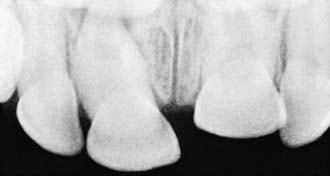

Intruded teeth are pushed up into their socket, sometimes to the point where they are not clinically visible. Intruded primary incisors can give the false appearance of being avulsed (knocked out). To rule out avulsion, a dental radiograph is indicated (Figs. 306-2 and 306-3).

image

Figure 306-3 Occlusal radiograph documents intrusion of “missing tooth” presented in Figure 306-2.